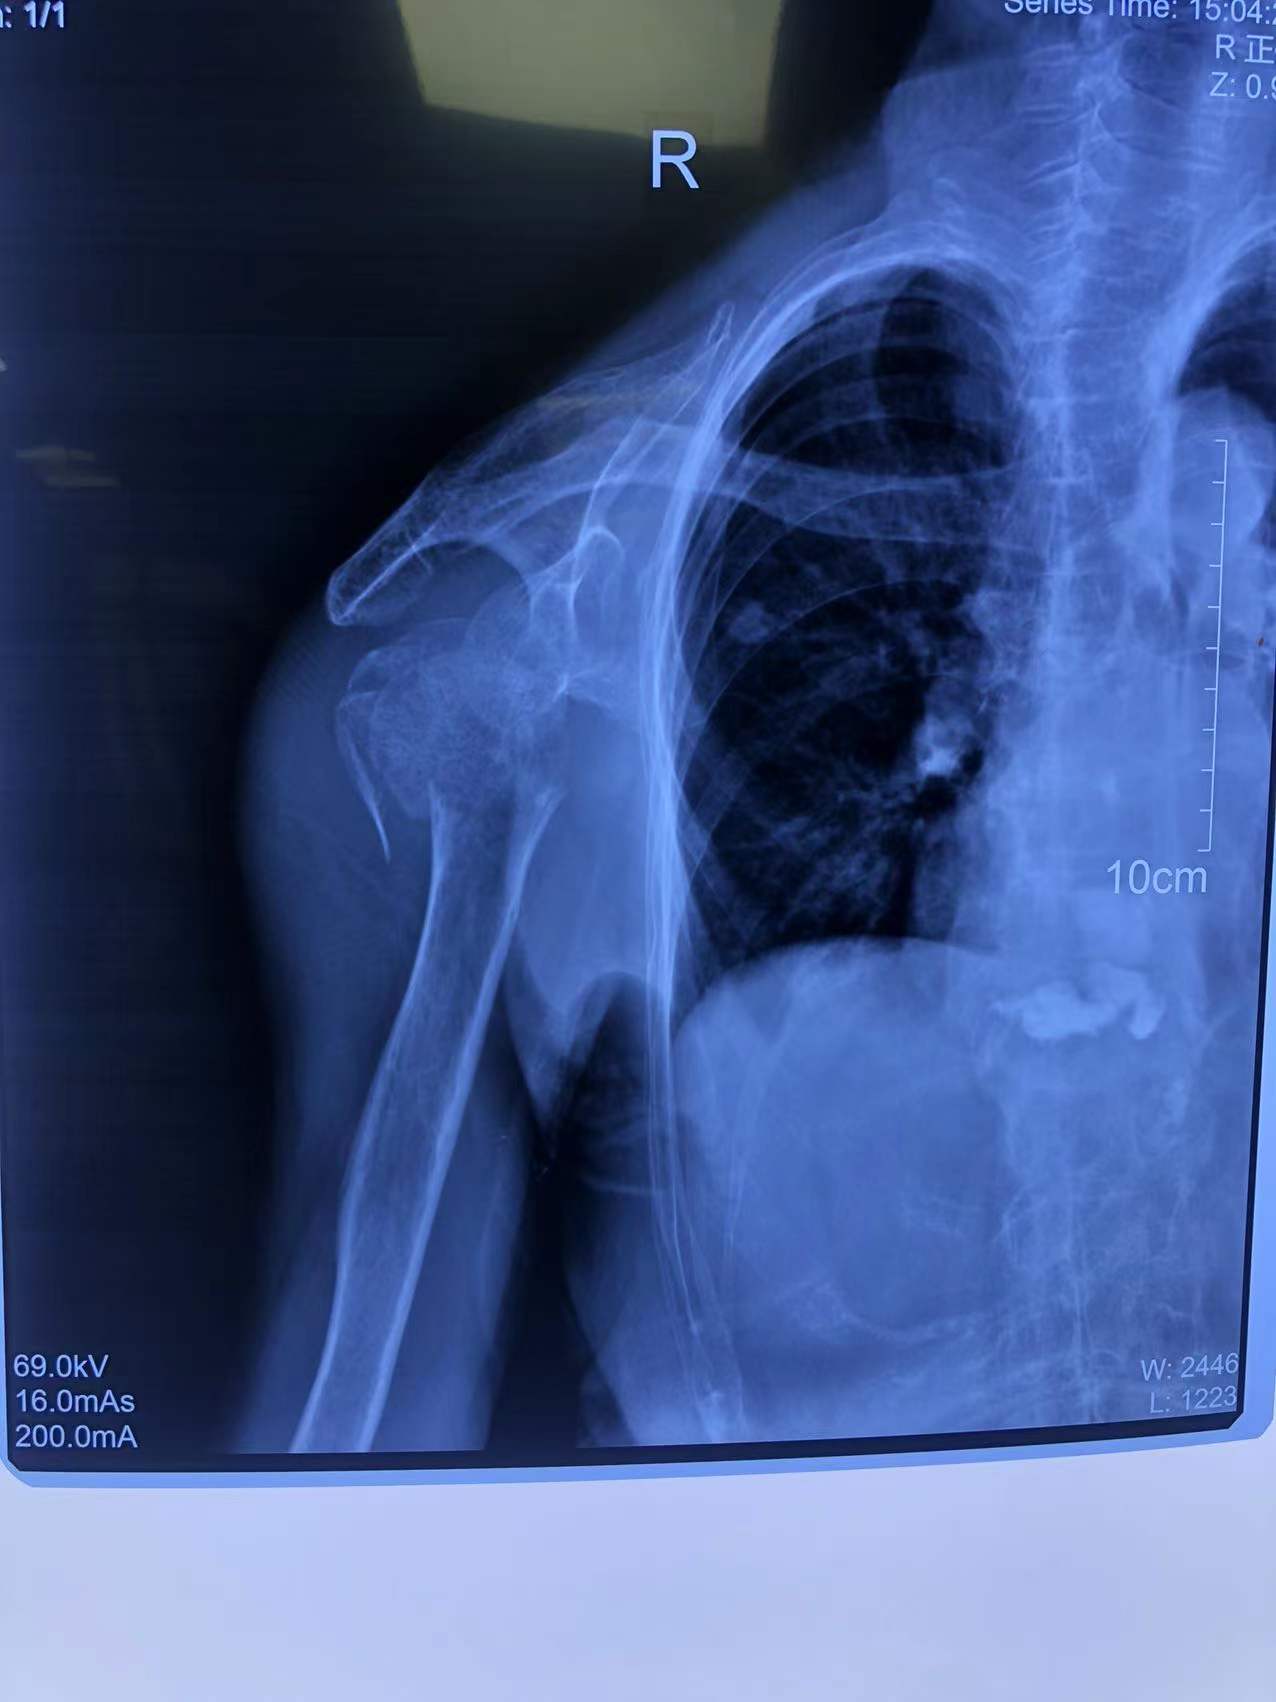

80歲的李老太(化名)走路時不慎摔了一跤,雖然感覺右肩膀和上臂疼痛劇烈,但她想著休息休息就沒事兒了,便沒有第一時間前往醫(yī)院看診。然而,接下來的幾天,疼痛不但沒有好轉(zhuǎn),反而愈演愈烈,這才被家人著急忙慌送到了石化醫(yī)院。行右肩X線檢查,原來,李老太右肱骨近端粉碎性骨折,隨后收住骨科。

李老太是粉碎性骨折,情況較為嚴重,為恢復肩關(guān)節(jié)功能,石化醫(yī)院骨科副主任張明龍帶領(lǐng)團隊充分評估病情,與病人和家屬協(xié)商后,決定實施人工肱骨頭置換術(shù),在右肩安裝一個“人工肩關(guān)節(jié)”。